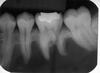

You perform an excisional biopsy on a radiolucent lesion of the mandibular premolar region. A representative section from the specimen is shown below. What is the best diagnosis? a. Lateral periodontal cyst b. Odontogenic keratocyst c. Glandular odontogenic cyst d. Ameloblastoma e. Calcifying odontogenic cyst

a. Lateral periodontal cyst The image shows the architecture of a cyst, including a lumen, epithelial lining, and fibrous connective tissue wall, therefore choice D is incorrect. The exact type of cyst is determined by the features of the epithelial lining. The lining shown is thin (1-3 cell layers thick) with focal thickenings. The diagnosis is therefore A, lateral periodontal cyst. An odontogenic keratocyst (B) will have a lining that is ~6-8 cell layers thick, has a palisaded basal cell layer, and is covered by a corrugated surface of parakeratin. A glandular odontogenic cyst (C) will have a lining of variable thickness and other features including mucous cells, apocrine snouting, microcysts, and cilia. A calcifying odontogenic cyst (E) will have aberrant keratinocyte formation known as “ghost cells.”